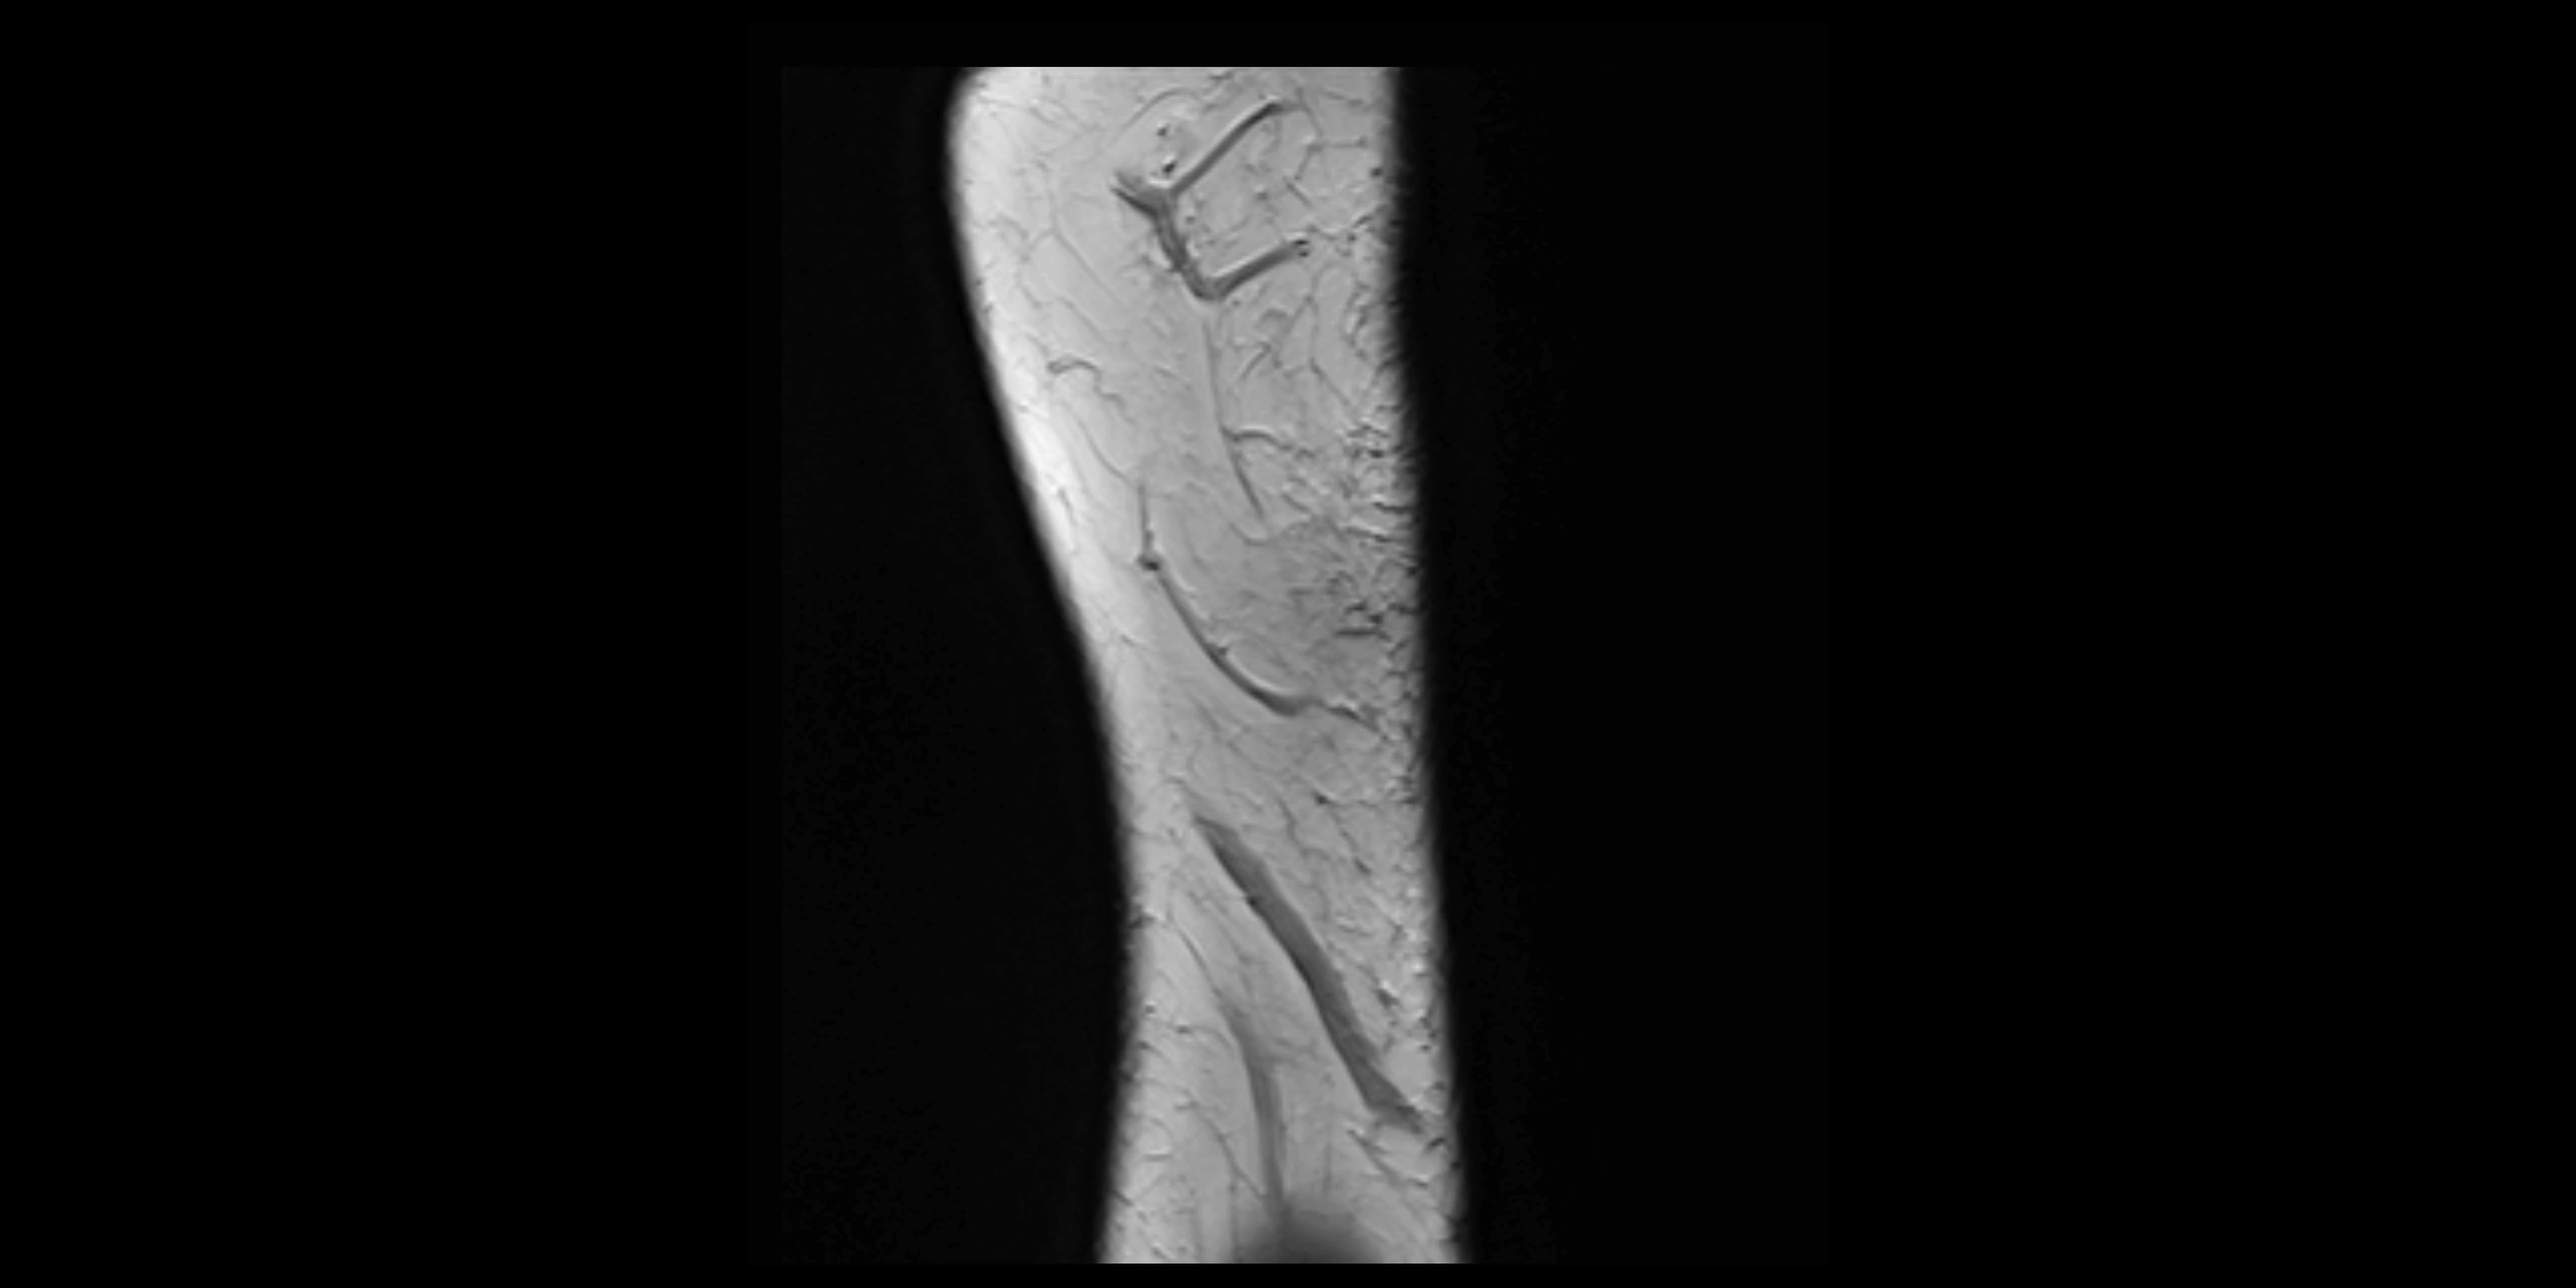

MRI images

image